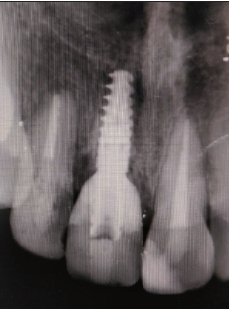

种植盾构术修复前牙外伤1例

在上颌前牙区唇侧骨板血供主要来自牙周膜及牙龈。当该位置牙缺失后,因为牙周膜来源的血供丧失,唇侧骨板常发生不同程度的吸收,从而造成唇侧软硬组织的塌陷,为最终的美学修复带来极大挑战。为了避免牙缺失后唇侧软硬组织的缺损,口腔医生以及研究人员提出了多种解决方案。其中,Hürzeler团队在2010年提出的“盾构术”(socket shield technique)的方式取得了较好的临床效果。本文报告笔者应用该技术对1例前牙外伤患者进行治疗,成功保留了患者软硬组织三维轮廓的完整性,实现了较好的美学效果。

The blood supply of the labial bone in the anterior teeth mainly relies on periodontal ligament and gingiva. Once tooth in this area is lost, blood from the periodontal ligament would disappear, and the labial bone would then collapse. Many solutions have been proposed to avoid this situation and retain the aesthetics of the dentition. Among these solutions, the “socket shield technique” reported by Hürzeler in 2010 acquired satisfying results. In this study, we applied this technique for the treatment of a patient whose right central incisor was broken in an accident and obtained a satisfactory aesthetic result.